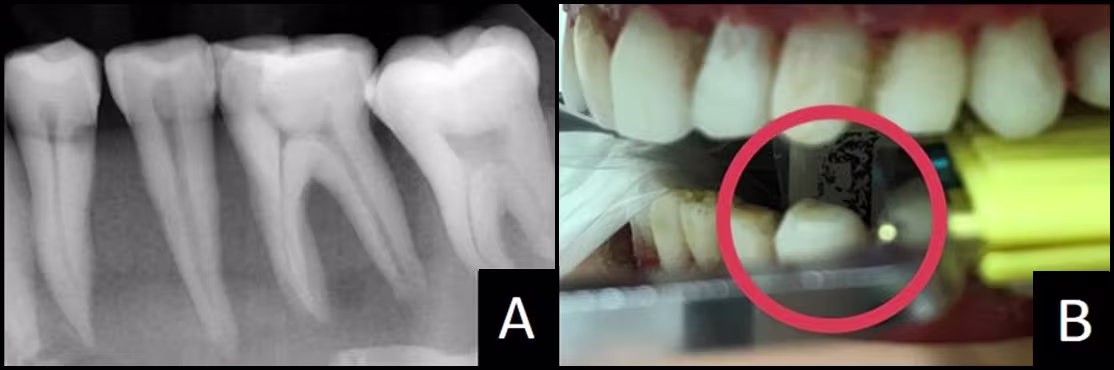

You must identify the correct horizontal angulation, and when standing in that path, make sure the active part of the sensor is physically within the radiation’s path. In Figure 9B, the photograph was created when standing in the correct horizontal angulation to capture the distal canine crown and to open the contacts around the first premolar. We can see active sensor positioned behind the canine #22 (within the green circle). The distal half of canine #22 and the premolars appear in the periapical image. In Figure 10, canine #22 does not appear in the image. Looking through the aiming ring, we see the sensor’s dead zone behind the canine. This can be difficult to correct. Keep reading and find solutions in Problem #3.

Figure 10 - Premolar Periapical

(A) Image without required distal crown #22.

(B) Deadzone behind #22 within red circle... tooth will not appear on the image.